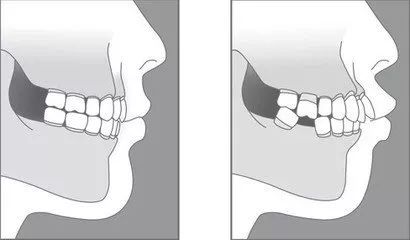

牙齿三缺一,不补会怎样? 危害一:临牙松动,又掉两颗 牙齿缺失后,相邻的牙齿会因为没有固定的依靠,向缺牙间隙倾斜,时间长了会造成周围邻牙的松动,致使全口牙齿的正常功能... 详情

缺牙久了,种是可以种,但过程会比较坎坷 所以在缺牙之后就一定要及时去补牙 否则拖长了时间真的没有好处! 咬合关系破坏,需要咬合重建 对颌牙伸长、邻牙倾倒、余牙移位时间越... 详情